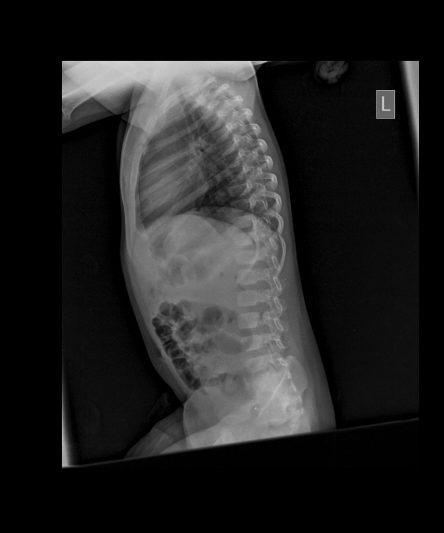

Microskan with Ultra high frequency can take the Lateral Lumbar Spine image of a 90 kg Patient with the correct image receptor